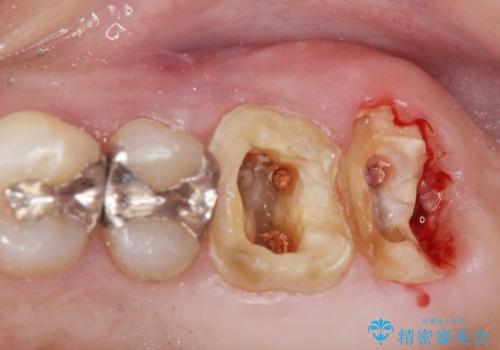

- 銀歯をやりかえたいが他院で抜歯と言われセカンドオピニオンで来院。適合の悪い被せ物が入っており、まずは古い材料、虫歯をとり保存可能か確かめる必要があり、拡大鏡下で全て取り除いたら歯質が歯茎の中まで虫歯がありました。このまま無理やり型取りをして被せ物を作っても不適合な被せ物が入る可能性が高いため歯茎を切り取る手術(ディスタルウェッジ)を行いました。そして再根管治療を行いゴールドの被せ物で治療を行いました。

- PGAクラウン・仮歯 13.2万円×2 精密根管治療(リトリートメント)・コア 16.5万円×2 ディスタルウェッジ 1万円費用は治療当時の料金となります

適合の良い被せ物が入り大変満足して頂けました。